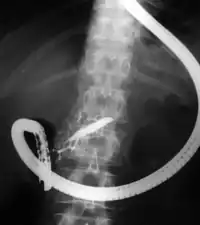

Fluoroscopic image of common bile duct stone seen at the time of ERCP. The stone is impacted in the distal common bile duct. A nasobiliary tube has been inserted.

Fluoroscopic image showing dilatation of the pancreatic duct during ERCP investigation. Endoscope is visible.